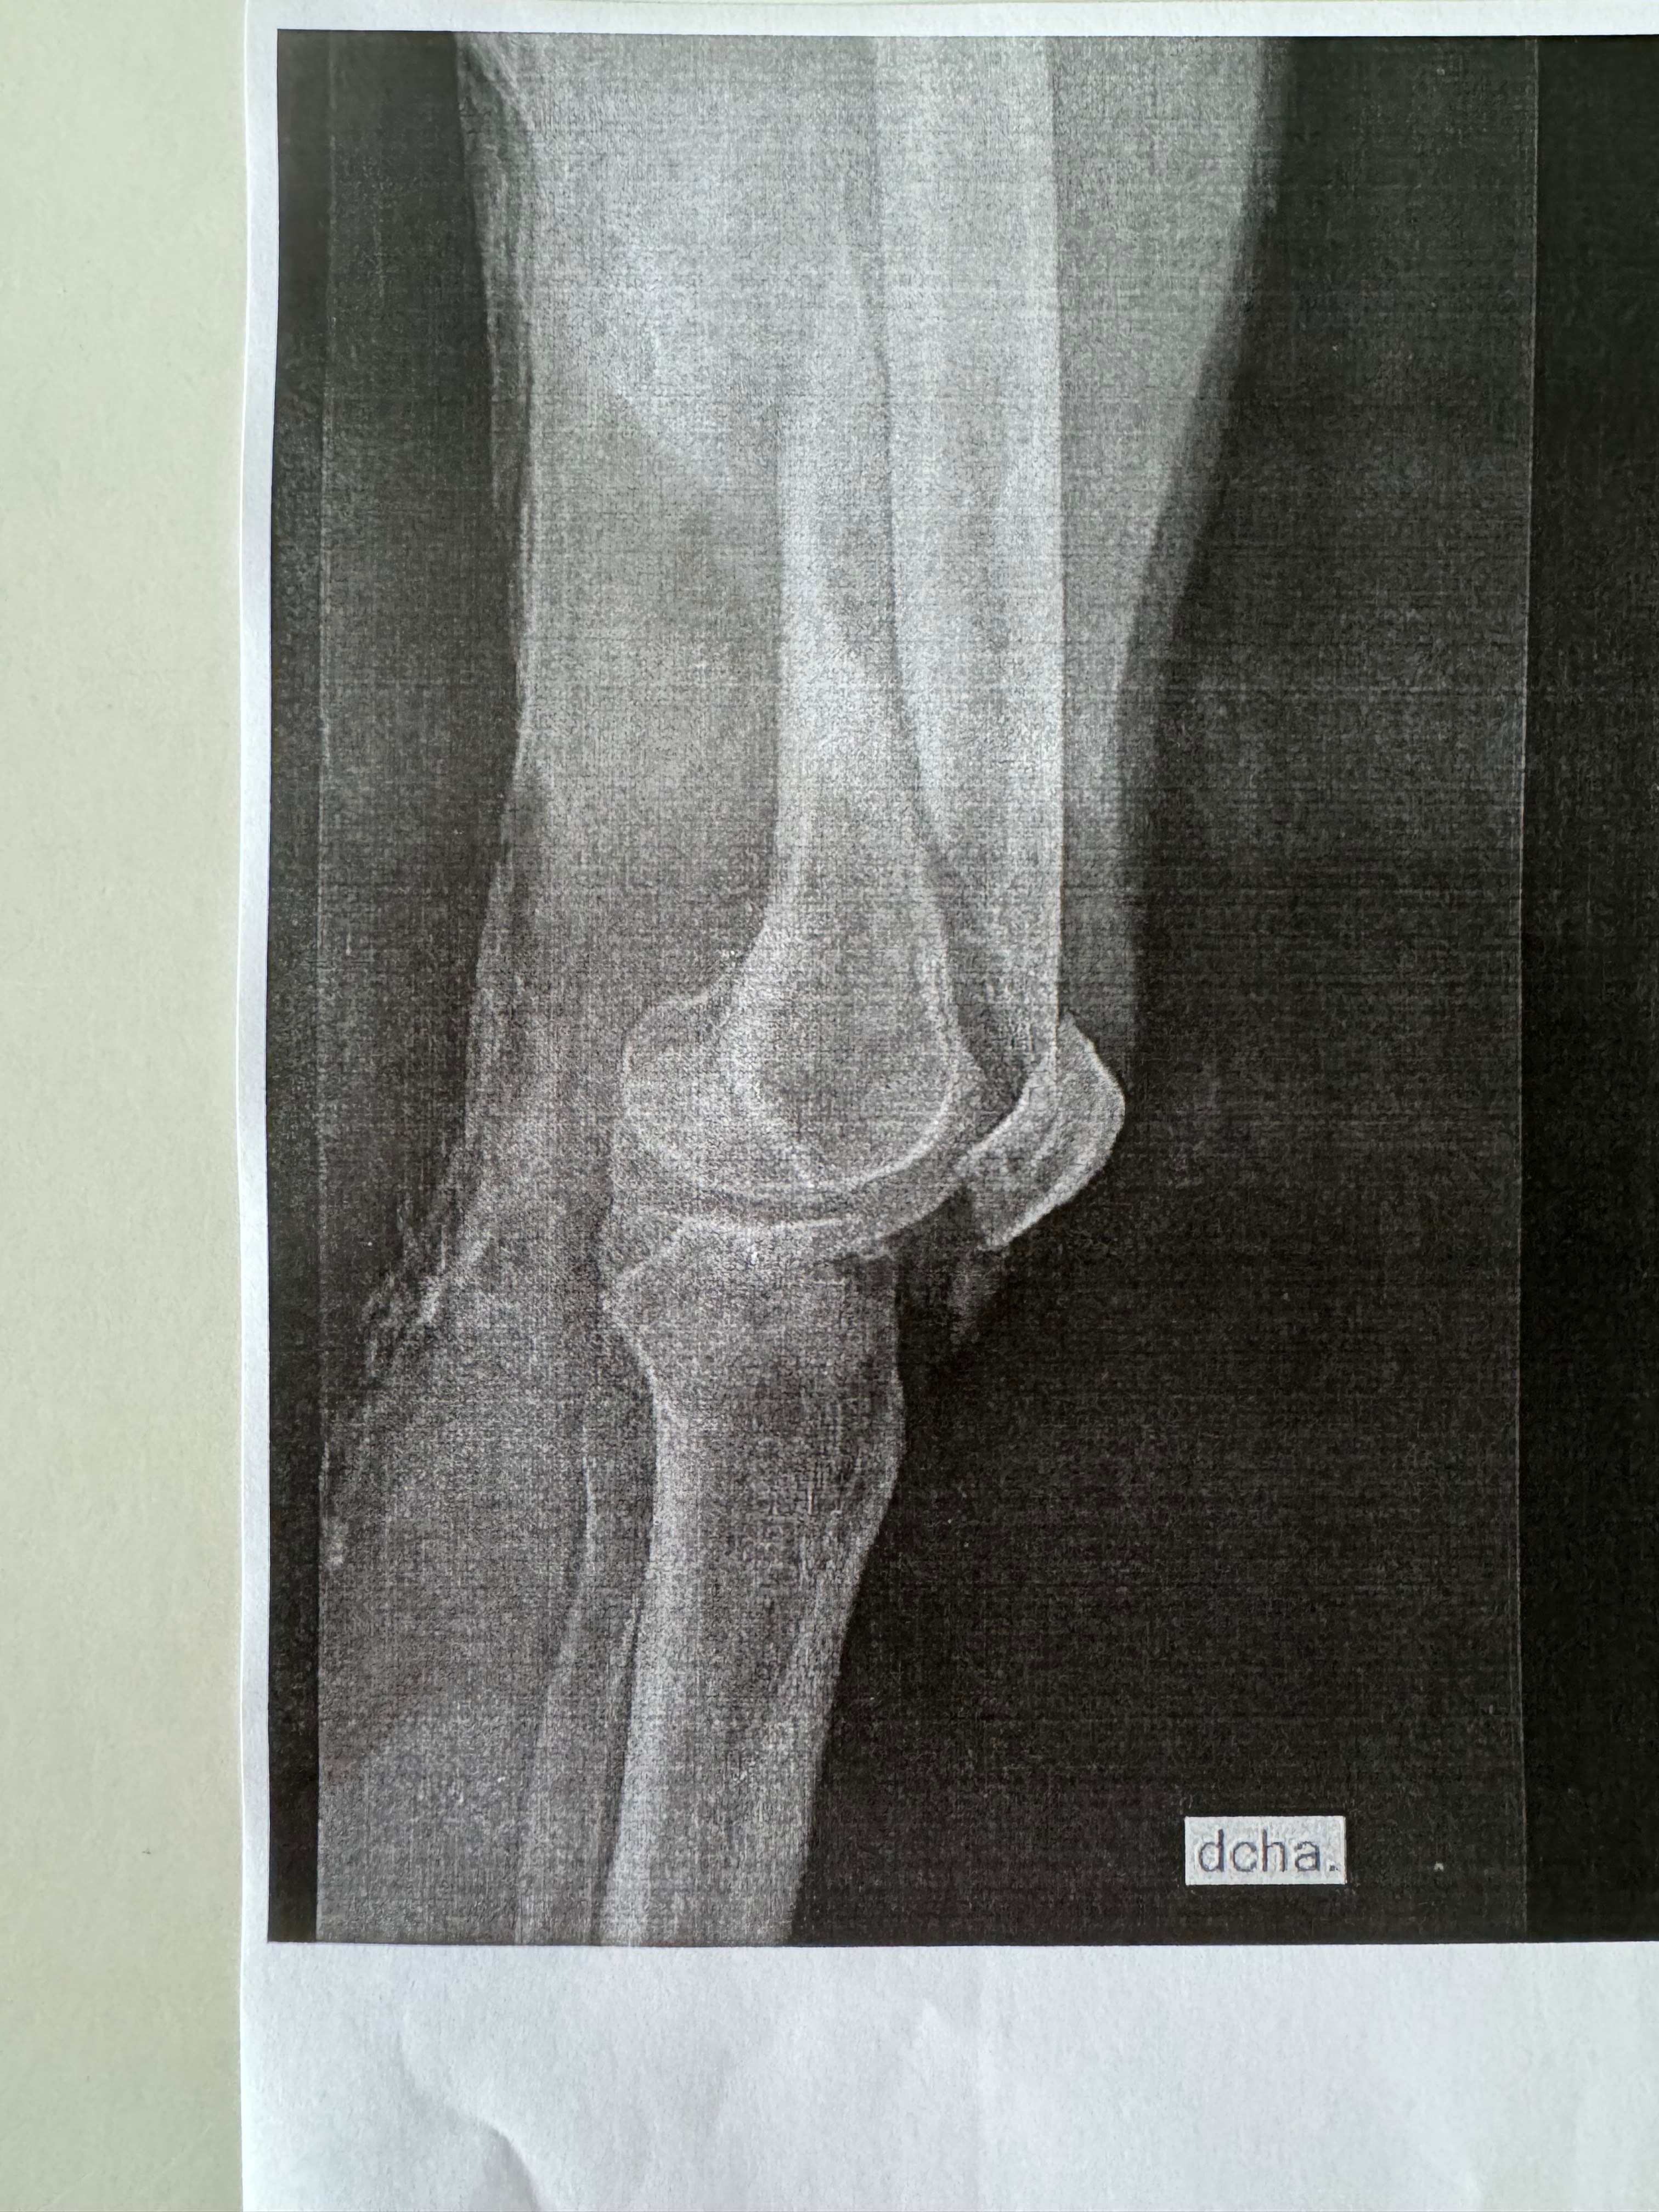

Deedee had an unforeseen accident that resulted in multiple fractures of her right leg. These injuries required an urgent surgery to stabilize her femur, she will need a second surgery for the tibial plateau fracture in the US. But first we need to get her home as soon as possible. We are requesting help for the overwhelming cost of medical care, extended stay, and the need for business class transportation home to accommodate her injuries.